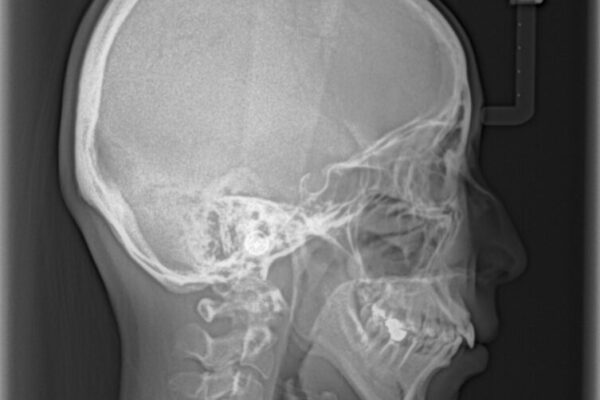

口元の閉じにくさと、奥歯の咬み合わせを気にして来院された患者様です。

左下の大臼歯2本が顕著に舌側に傾斜しているため、まずは奥歯の咬み合わせを改善をし、その後上下左右の第1小臼歯4本を抜歯することで口元を引っ込めながら整えることとしました。

奥歯の咬み合わせ改善には1年ほどの期間と処置中の噛みにくさを強いることとなりましたが、抜歯後はスムーズに治療を完了させることができました。

歯ぎしりの際に奥歯が干渉していた咬み合わせも理想的な状態に改善できました。

• 【モニター】出っ歯と咬み合わせを改善 ワイヤー装置の抜歯矯正 治療前画像